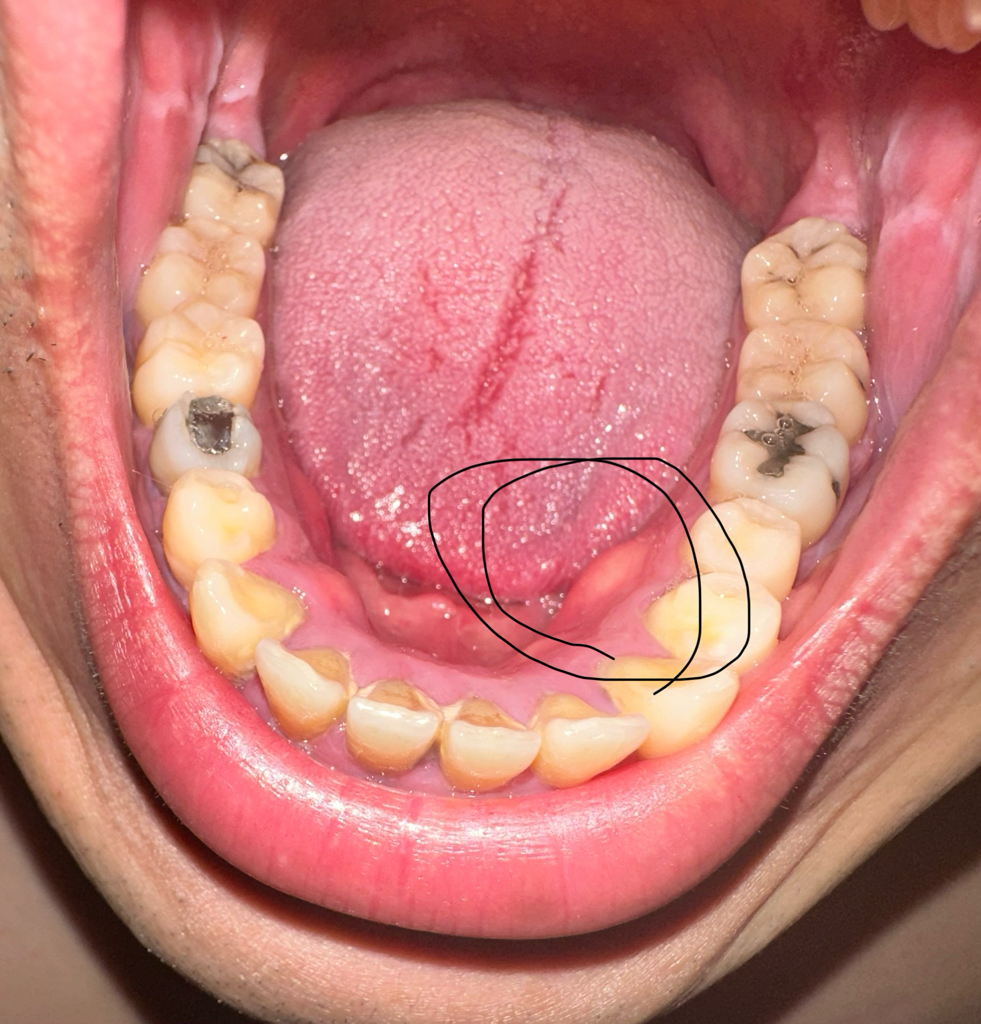

안녕하세요. 이욱현 의사입니다. 피와 고름이 나오면 치과 또는 이비인후과 진료를 받는 것이 좋을 것으로 보입니다. 항생제 치료가 필요할 것으로 보이며 염증이 어느 정도 범위인지 확인이 필요하겠습니다.